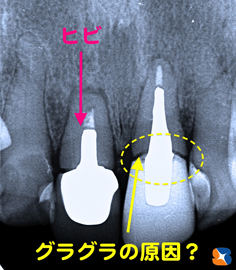

クリスマス日の朝、30代の自営の男性。主訴は「事故で前歯を損傷した。」とのこと。マイクロスコープ等で患部を精査すると差し歯の根が割れていることが判明しました。

抜歯の必要性を伝えたところ、「元々歯並びも悪かったので、前歯3本ともキレイにしたい。抜いた所はインプラントにする。」とのことでした。

これは、抜歯した日にそのままインプラントを移植したところのレントゲン写真です。

もう1本のグラつきは、差し歯の外れかけが原因では?と予測していましたが、歯の根面に亀裂が入っている事を手術で確認しました。

左の写真は、抜歯したその日にインプラントを埋めたところです。同様に隣りのひび割れした歯も「抜歯→インプラント埋め」をその日のうちに行います。